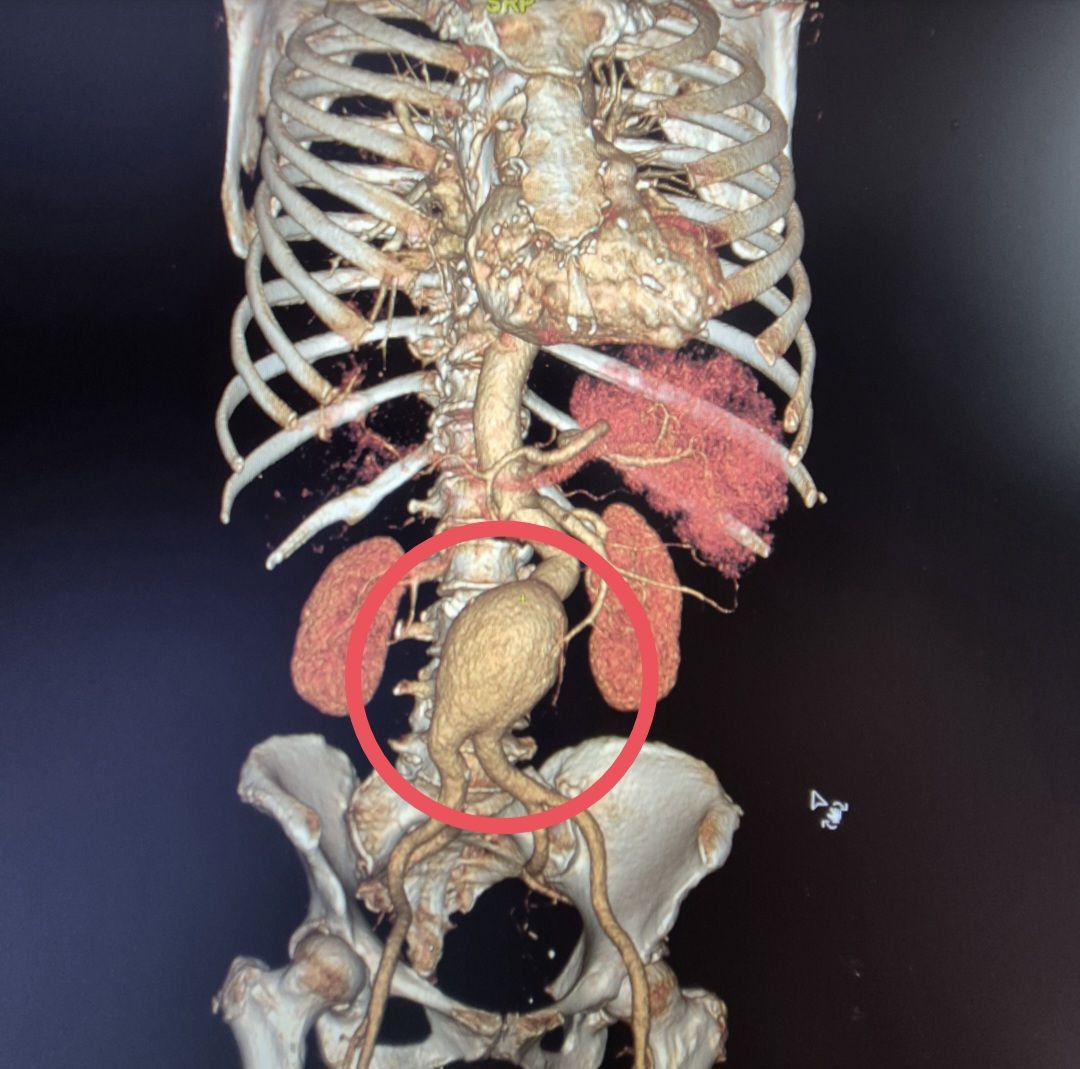

Балаковские хирурги прооперировали женщину с "бомбой замедленного действия"

В Балаковскую городскую больницу поступила 60-летняя женщина с сложным диагнозом - мешотчатой аневризмой брюшной аорты. Аневризма брюшной аорты считается "бомбой замедленного действия", а мешотчатая форма особенно опасна из-за риска мгновенного разрыва.

За лечение пациентки взялся заведующий отделением сосудистой хирургии Балаковской больницы. Операция длилась более шести часов и прошла успешно.